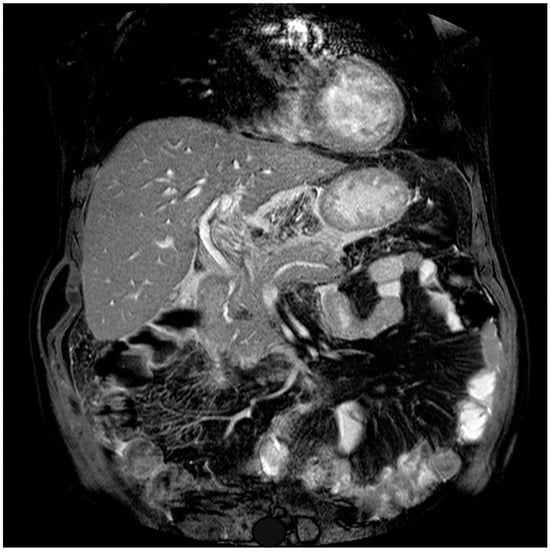

4. Case Presentation